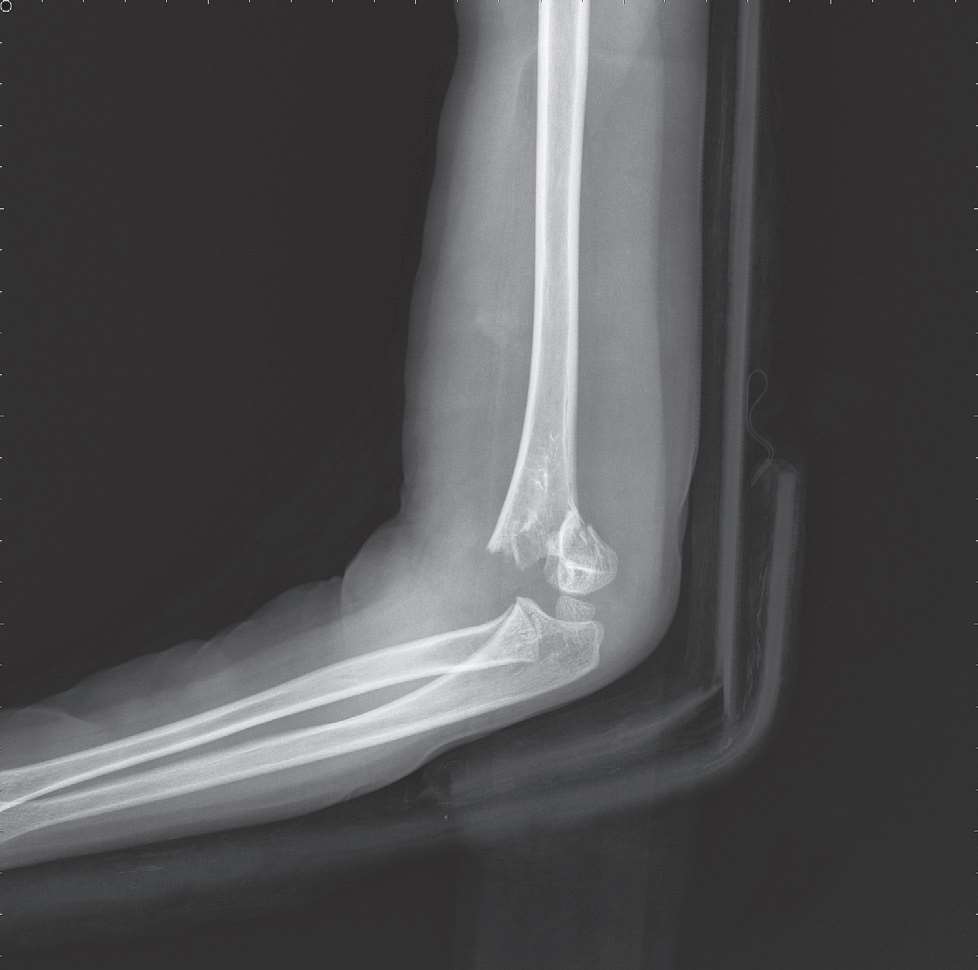

3.影像学检查(图6-1)。

图6-1 肱骨髁上骨折X线片